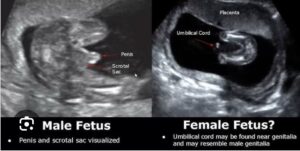

يستطيع الطبيب المساعدة على تحديد نوع الجنين بالبحث عن شكل اعضاء الجنين الذكر والتي تظهر في تصوير السونار بشكل غطاء السلحفاة وتسمى علامة السلحفاة turtle sign كما يتضح في الصورة التالية.

بينما تظهر اعضاء الاجنة الإناث في شكل ثلاثة خطوط متوازية ويسمى هذا الشكل علامة البرجر (كأن الثلاثة خطوط هم شطيرتي الخبز بينهما البرجر) كما يتضح في هذه الصورة.

وفيما يلي بعض صور السونار التي يمكن ان تساعدك على التفرقه بين الاجنة الذكور والاناث في تصوير السونار.